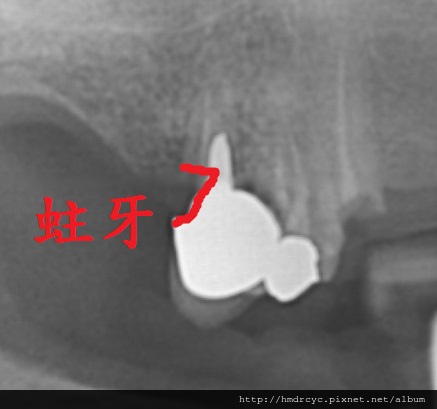

假牙必須利用X光片來更精確的判斷有沒有問題

在X光上面假牙是白色的影像

但X光片判讀困難 所以這部分必須仰賴醫師的專業

1. 蛀牙

蛀牙是常見的問題

臨床上可以在牙套邊緣勾到空隙

X光上則是一個黑色的蛀洞可以參考蛀牙範圍

X光通常會有1-2mm的誤差

所以實際上牙齒裡的洞會比影像大

只要牙套底下出現X光可以辨別的蛀洞

未來繼續蛀牙的速度會很快

牙套內的牙齒也會流失的很嚴重